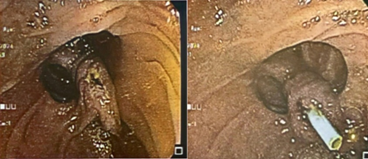

Se realiza una colangiopancreatografía endoscópica retrograda (CPRE), donde se identifica Papila de Vater intradiverticular que dificulta el acceso a la vía biliar principal, se realiza precorte, sin embargo, la canulación de la vía biliar fue fallida. (Figura 1)